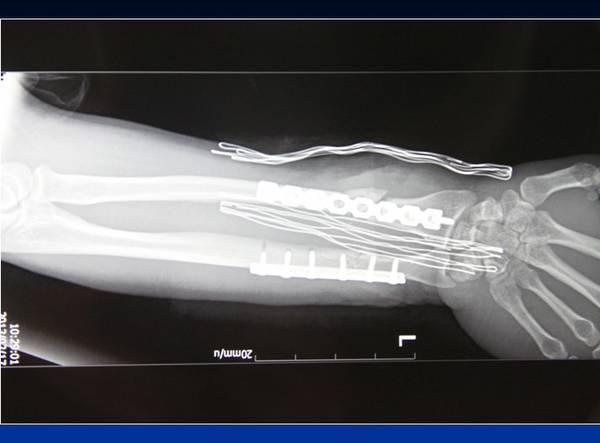

经典病例

省立医院王德华主任作品

取对侧头静脉桥接桡动脉

取胫后动脉皮瓣,串联尺动脉